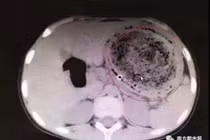

| Vì thói quen nhai mớm khi bà cho ăn, bé Lele bị nhiễm khuẩn Helicobacter pylori dẫn tới chảy máu dạ dày. (Ảnh Sohu) |

Ngay lập tức, bác sĩ đề nghị người thân của Lele kiểm tra. Kết quả cho thấy bà ngoại của bé đang có vấn đề về sức khỏe, cơ thể mang mầm bệnh. Trong khi các thành viên chưa hiểu hết sự việc, bác sĩ kết luận Lele mắc bệnh từ bà ngoại.

Cha mẹ của Lele cho biết thời gian gần bé được đưa về bà ngoại chăm sóc. Khi cho cháu ăn, bà sợ Lele không nhai được thịt nên đã nhai và mớm cho bé. Ngoài ra, khi pha sữa bà cũng dùng miệng để thử độ nóng và điều chỉnh lượng sữa bột.

Theo bác sĩ, Lele còn nhỏ, sức đề kháng yếu và niêm mạc dạ dày mỏng. Sau một thời gian dài ăn thức ăn nhai mớm nên nguy cơ nhiễm vi khuẩn Helicobacter pylori cao, dẫn tới tình trạng loét dạ dày gây chảy máu.